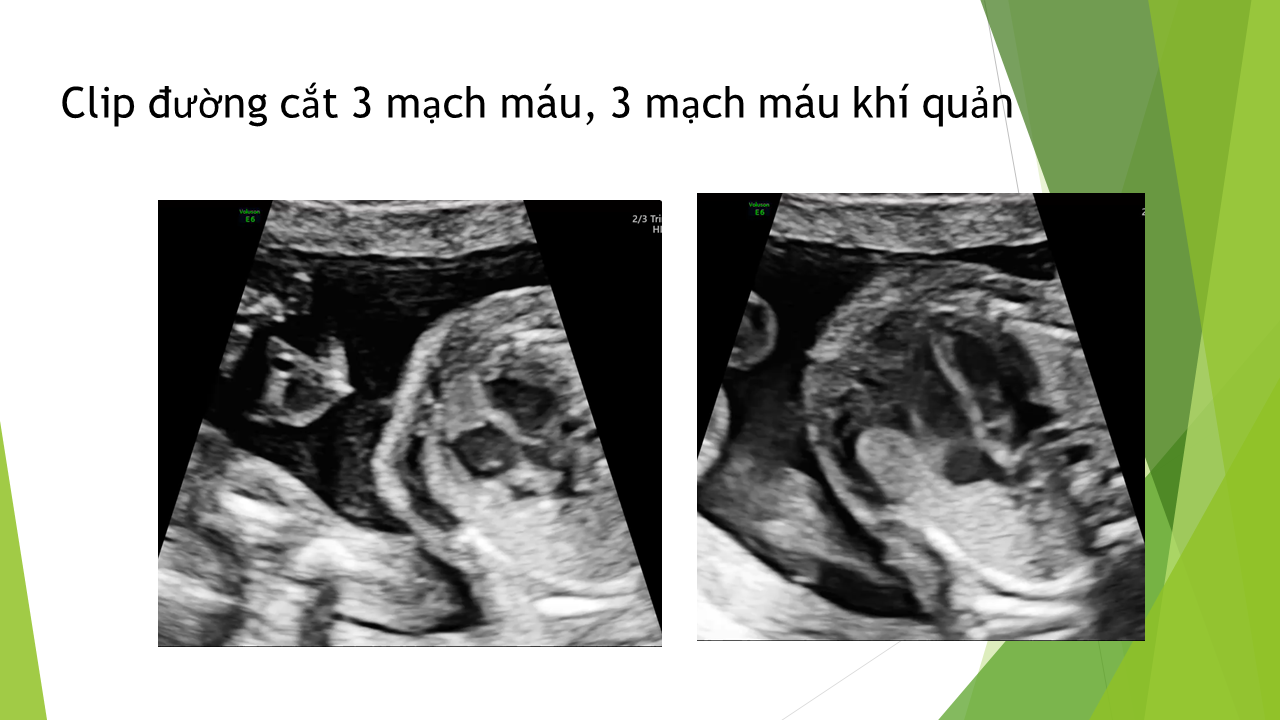

Siêu âm tim thai bằng phương pháp LEVY và STOS. 5-4-3-2-1